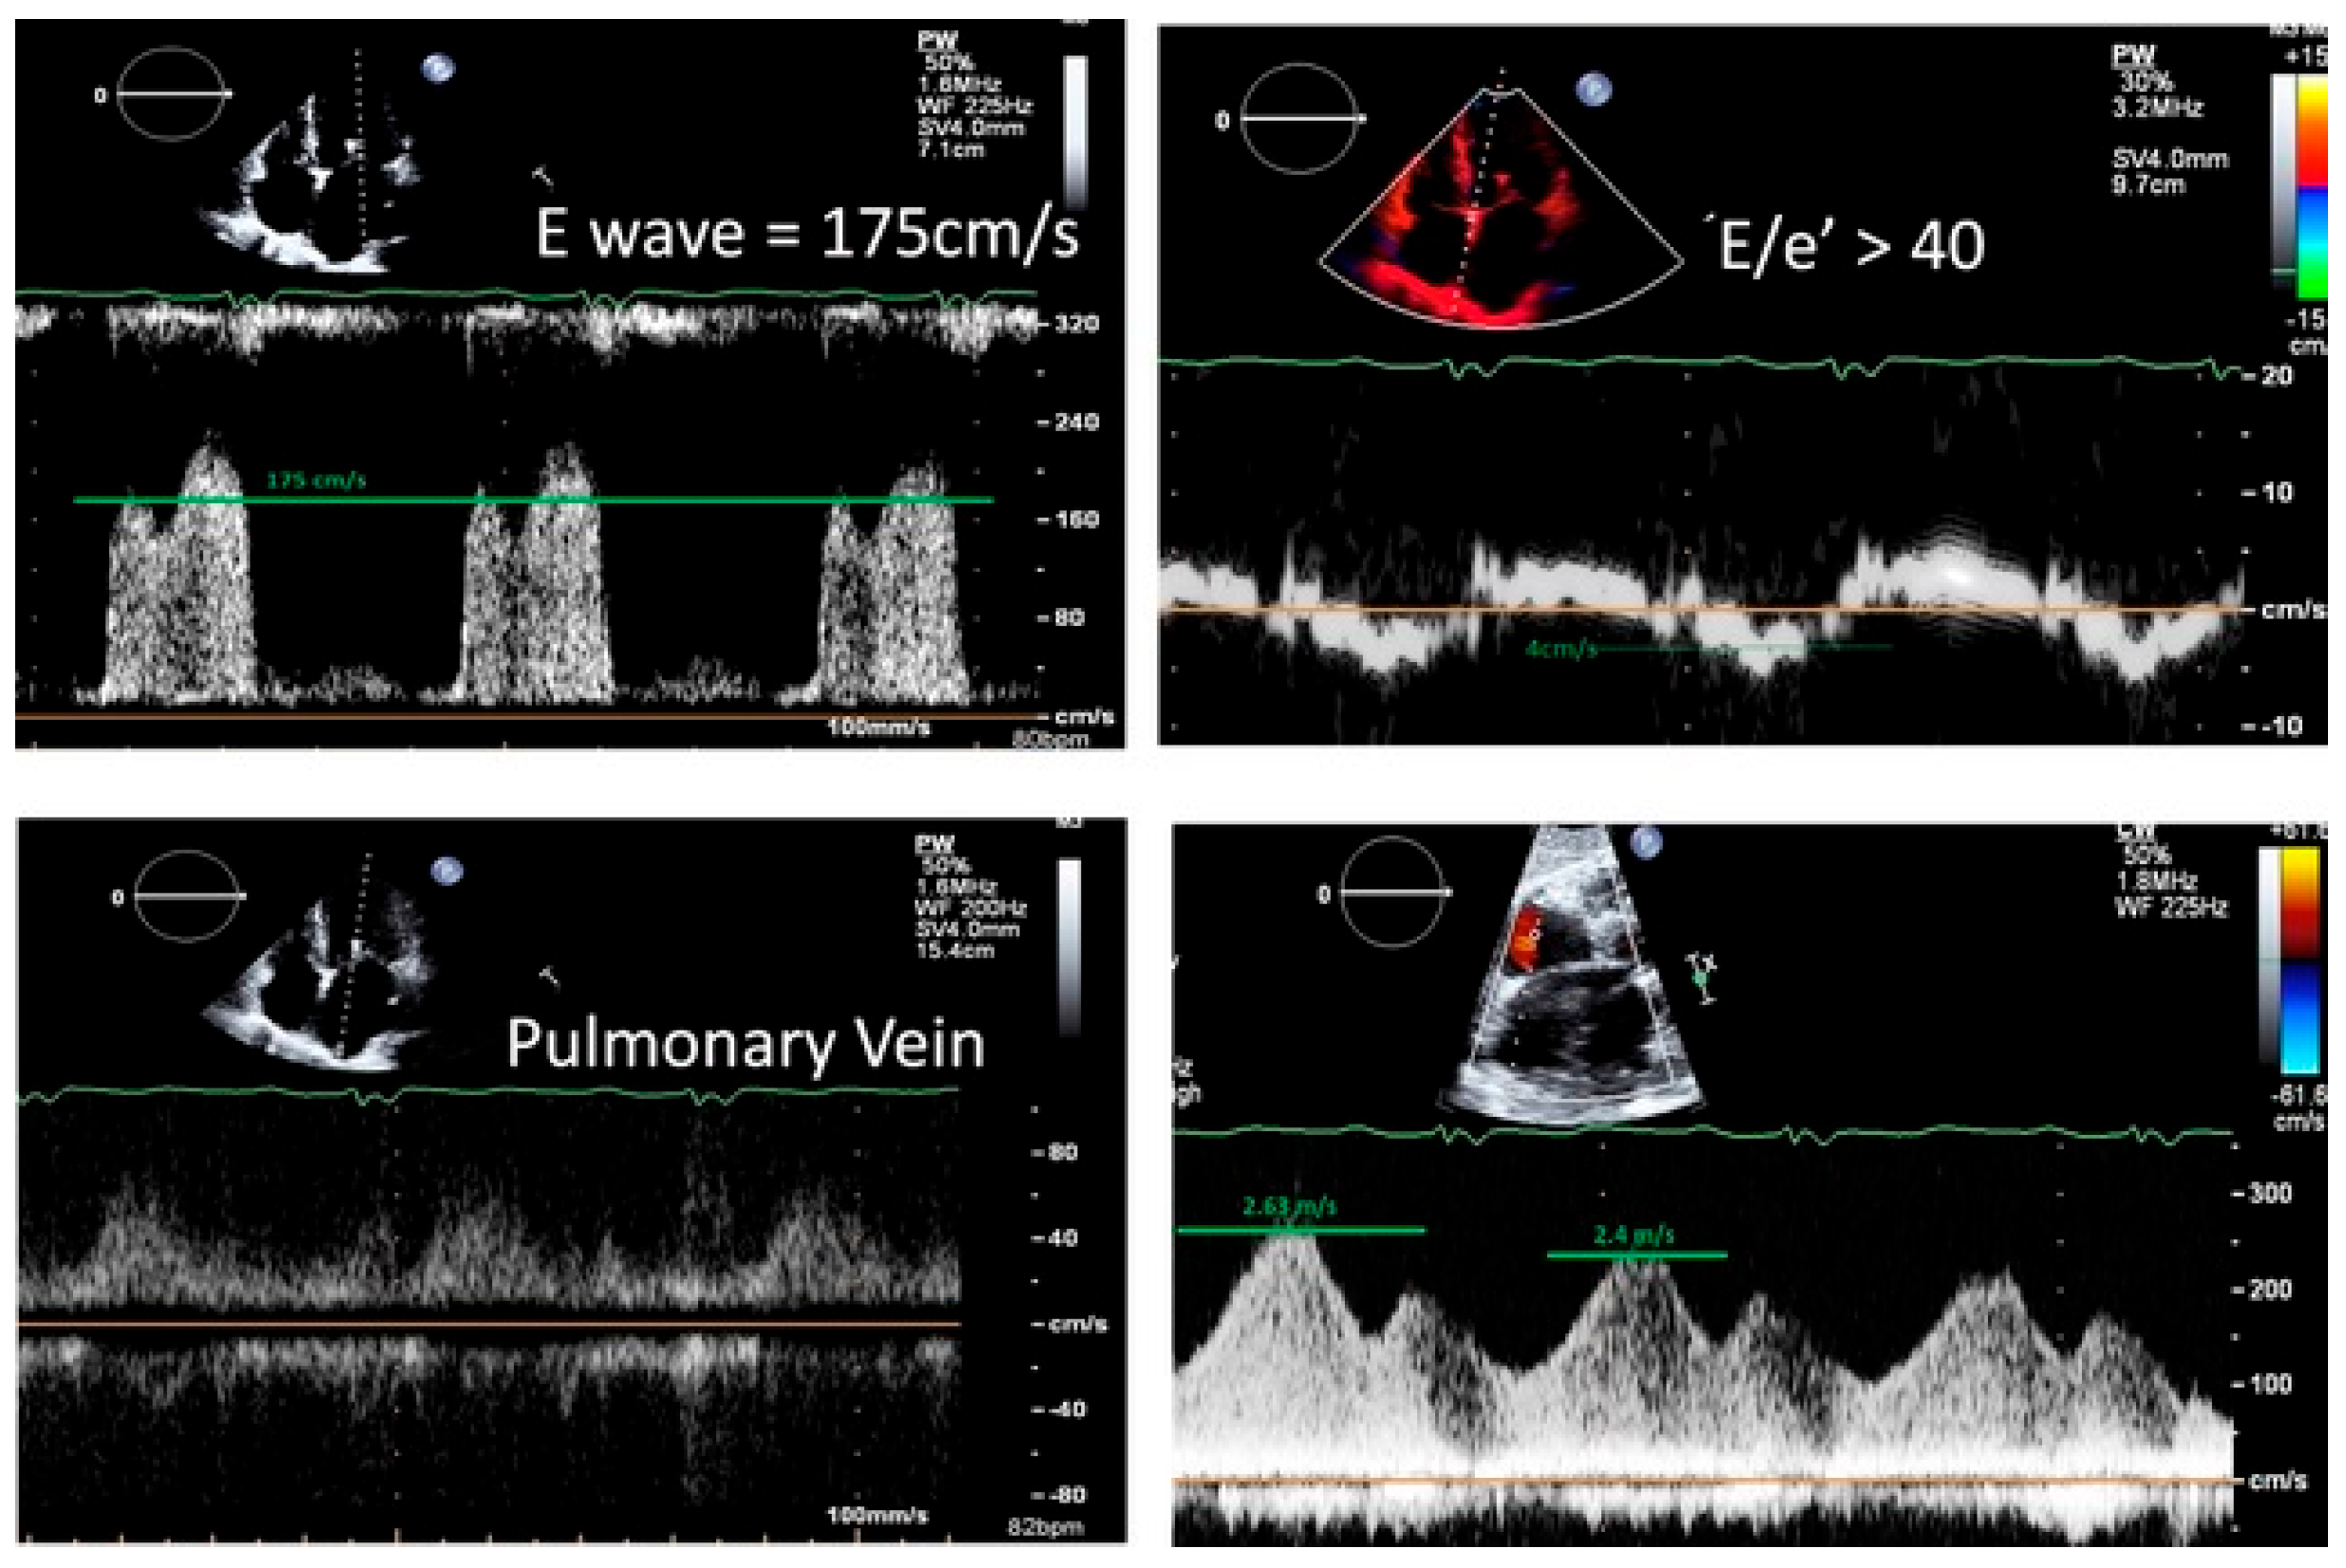

- Elevated LAP: Maximum E wave velocity > 163 cm/s

- Normal LAP: Maximum E wave velocity ≤ 85 cm/s

- Elevated LAP: Maximum E wave velocity > 158 cm/s OR E/e′ ratio > 34

- Normal LAP: Maximum E wave velocity ≤ 95 cm/s OR E/e′ ratio ≤ 14